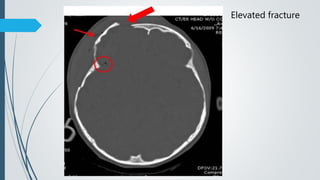

C. Elevated – elevated rotated skull segment

Elevated fracture